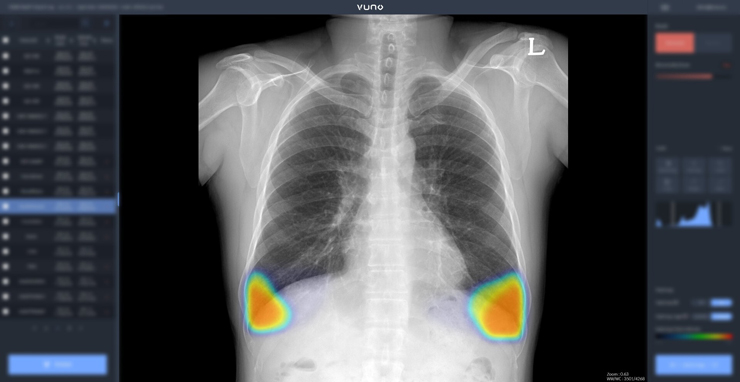

우즈베키스탄 국군 중앙병원 등에 공급된 솔루션은 AI 기반 상지 엑스레이 판독 보조 솔루션 ‘뷰노메드 익스트리미티 엑스레이’, 이동형 엑스레이 장비에 AI 기반 흉부 엑스레이 판독 보조 솔루션 ‘뷰노메드 체스트 엑스레이’를 탑재한 패키지 등 2종이다.

이동형 엑스레이 장비에 뷰노메드 체스트 엑스레이를 탑재한 패키지 제품은 별도의 차폐 시설 없이도 다양한 상황에서 쉽게 환자의 흉부 엑스레이 촬영과 판독을 지원하는 점이 특징이다.